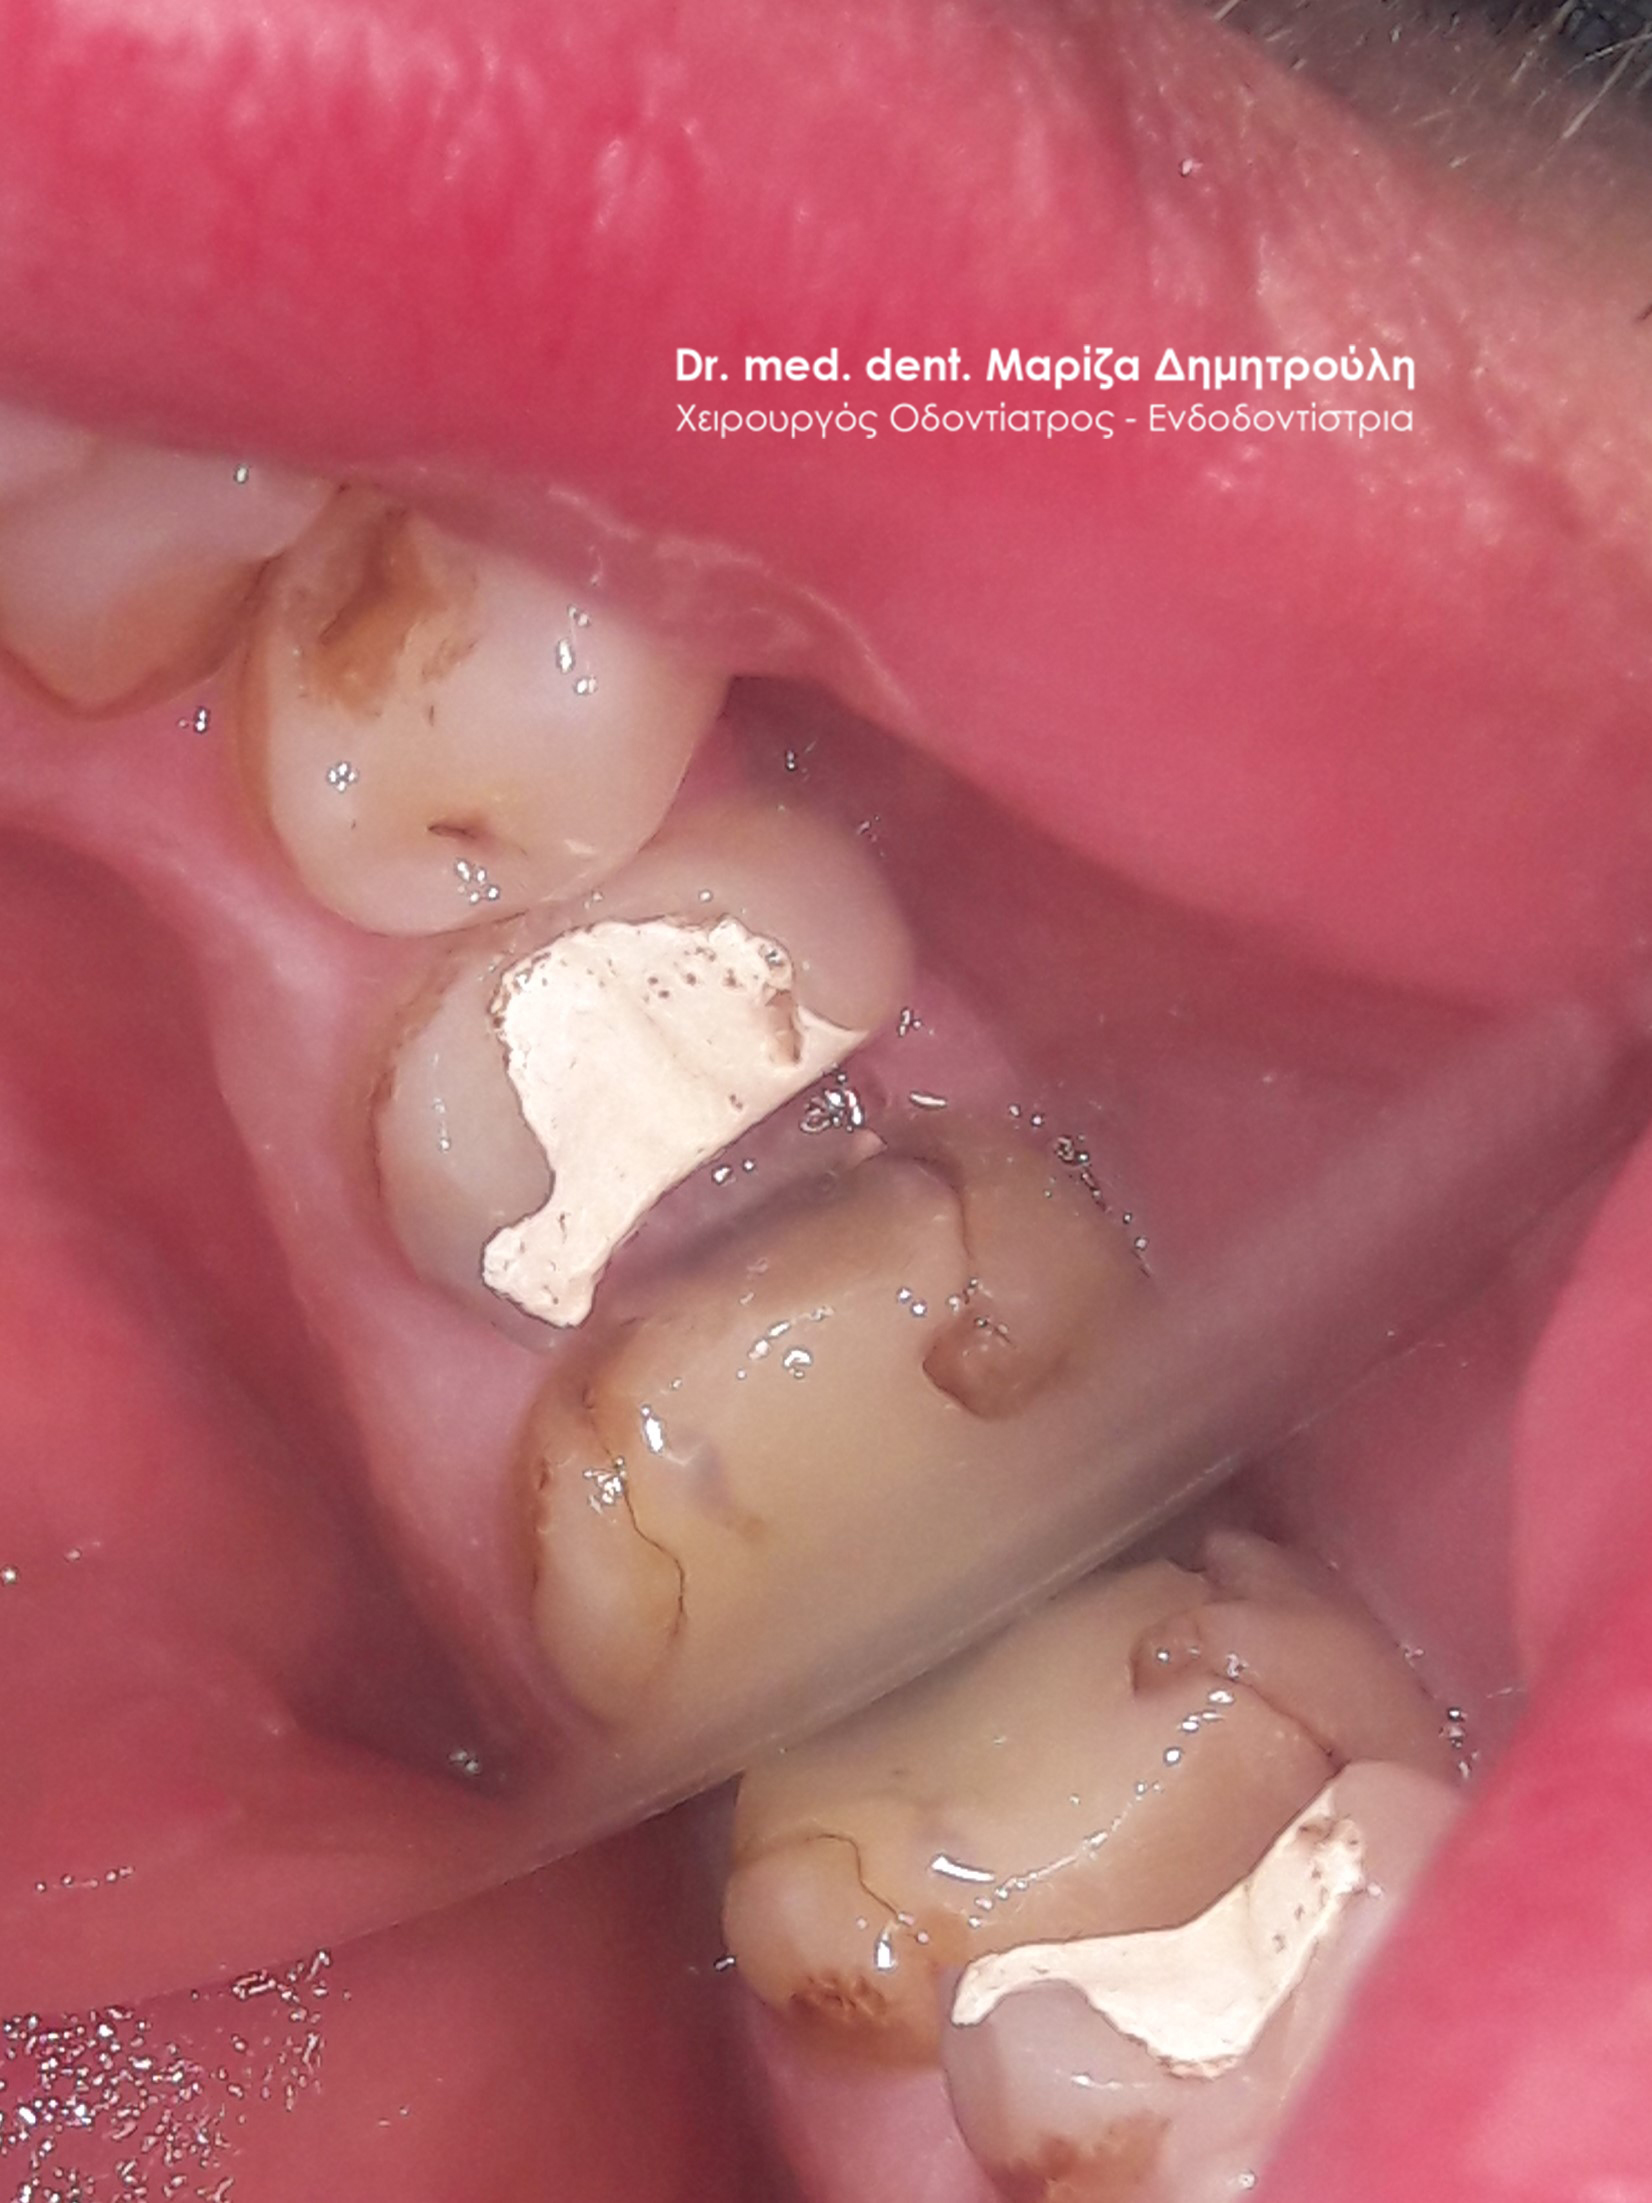

Ο ασθενής μετά το πέρας της ενδοδοντικής θεραπείας του δοντιού προτίμησε (για οικονομικούς λόγους) την αποκατάσταση του με λευκό σφράγισμα σύνθετης ρητίνης έναντι της τοποθέτησης θήκης δοντιού, η οποία σαφώς προστατεύει το δόντι με μεγαλύτερη ασφάλεια. Στο συγκεκριμένο δόντι επειδή απουσίαζε μεγάλο τμήμα οδοντικού ιστού δεν ήταν δυνατόν ένα απλό σφράγισμα ρητίνης να αποδώσει επαρκές σημείο επαφής με το παρακείμενο δόντι. Ο ασθενής ενημερώθηκε και δεν τον ενοχλούσε.

Στην προκειμένη περίπτωση οι οδοντίατροι θα πρέπει να ενημερώνουν τον ασθενή οτι υπάρχει μεγάλος κίνδυνος θραύσης τόσο του σφραγίσματος όσο και του απονευρωμένου δοντιού. Η τοποθέτηση θήκης σε απονευρωμένα δόντια με μεγάλο έλλειμμα οδοντικής ουσίας ενδείκνυται για προστασία από τυχόν κατάγματα δοντιού.

ΠΡΙΝ

META